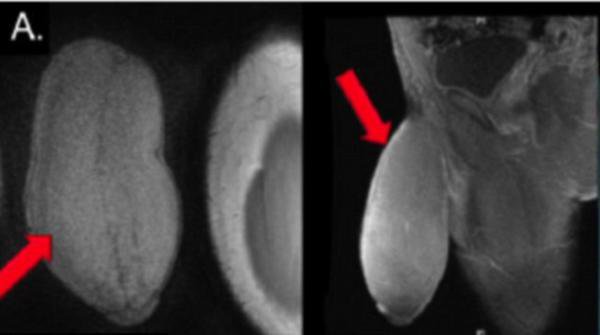

Les médecins qui ont eu affaire à l'adolescent ont expliqué que son pénis avait une forme «ressemblant à un ballon de football américain». «Dans la carrière de tout urologue arrive ce moment où un patient pose une question si rare et impossible à appréhender que toutes ses connaissances s'écroulent et le laisse sans voix. Cette question était: «Pouvez-vous rendre mon pénis plus petit?», a raconté Rafael Carrion.

Finalement, l'équipe a décidé de tenter une technique chirurgicale normalement utilisée pour traiter la maladie de la Peyronie, une sclérose qui provoque une déviation du pénis en érection. L'intervention a été couronnée de succès et deux jours après, l'adolescent a pu rentrer chez lui, ravi de son nouveau pénis. «Il est un peu plus long et un peu plus gros que la moyenne, mais il est symétrique et le patient était très satisfait», assure le Dr Carrion. L'histoire de cette première mondiale a été publiée dans la revue médicale «The Journal of Sexual Medicine».